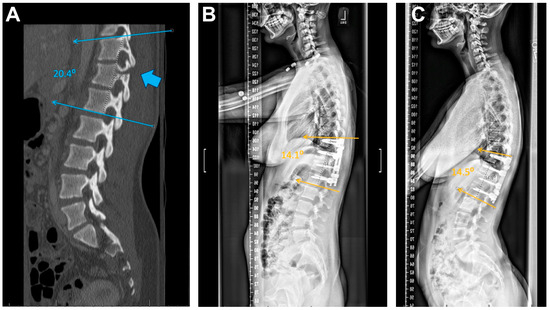

2.4. Alignment

3.7. Alignment

4.6. Alignment